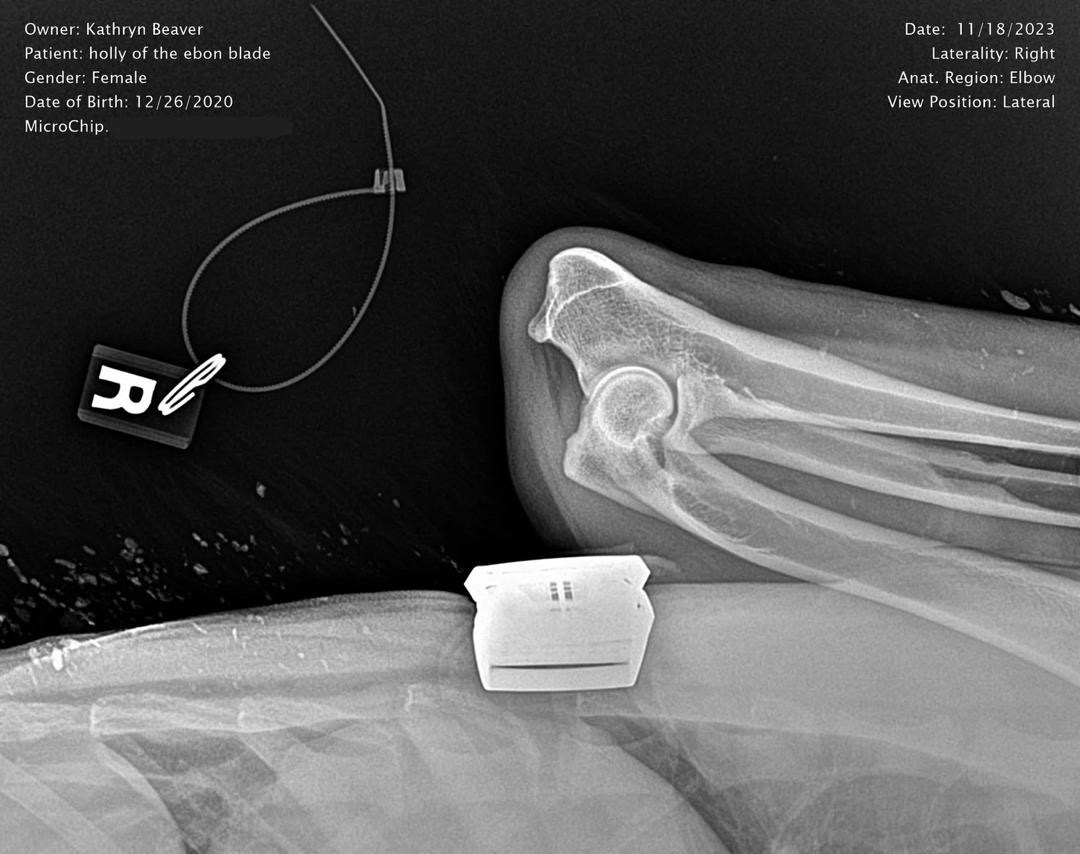

Holly Right Elbow X-Ray

Right Elbow X-Ray

OFA Elbow Evaluation: Normal